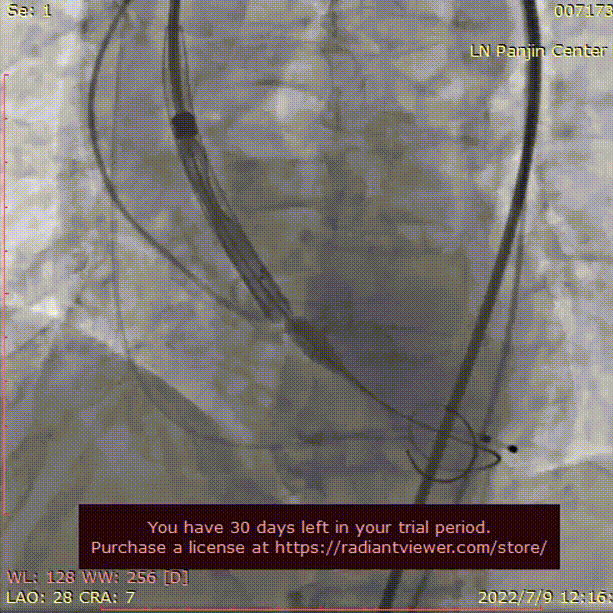

术中影像

主动脉根部造影

导丝顺利跨瓣

TaurusAtlas 20mm球囊

充分预扩张

无明显腰征 无漏

TaurusElite AV23瓣膜

瓣下2mm初始定位

工作位造影 位置满意

冠脉灌注良好

瓣膜最终位置造影

形态良好 无瓣周漏

即刻跨瓣压差为4mmHg